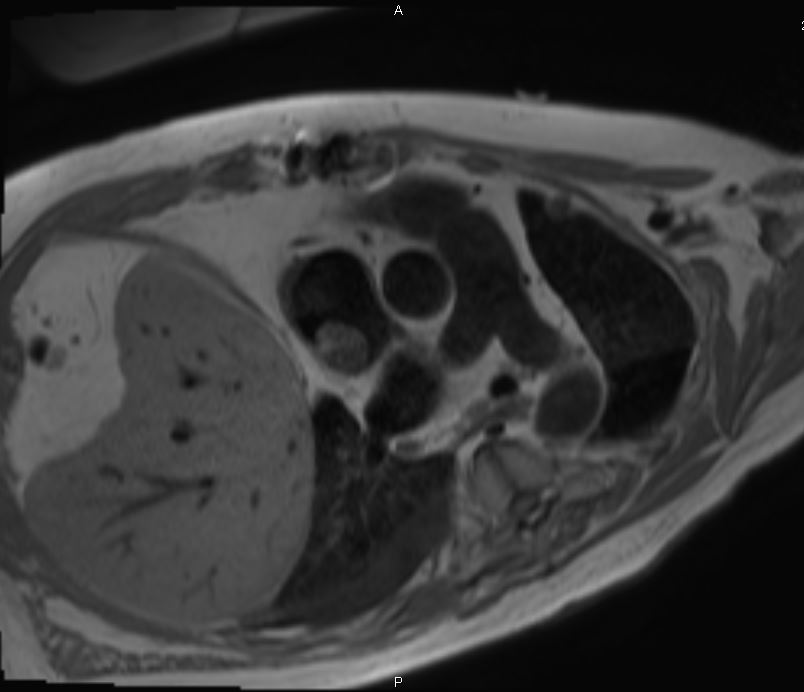

Cardiac MRI was performed on January 3, 2018, which revealed a large 2.5 × 2.9-cm lobular, fairly sessile mass in the right atrium. Without evidence of tissue destruction to suggest a malignant process, the lesion was suggestive of either myxoma or hematoma due to marked contrast uptake (which is seen less often with myxomas) (Figure 1).

Figures 1A-G. Cardiac MRI findings of a large, lobular, fairly sessile mass in the right atrium, measuring 2.5 x 2.9 cm, suggestive of either myxoma or hemangioma.